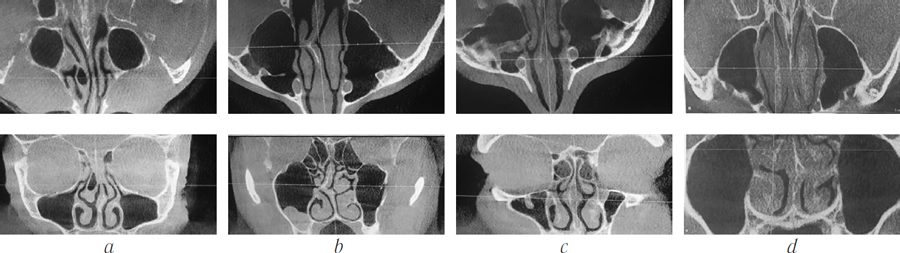

- nasal septum deviation (functionally significant): 5 patients (Fig. 1, a);

- swell body: 4 patients (Fig. 1, b);

- Соncha bullosa: 2 patients (Fig. 1, c);

- vasomotor rhinitis: 18 patients (Fig. 1, d).

Fig. 1. CBCT of the patient: concha bullosa right (a); nasal septum deflection to the right. Bilateral inferior nasal concha increase. Right maxillary sinus' cyst (b); Swell-body (c); bilateral middle and superior nasal concha increase (d)